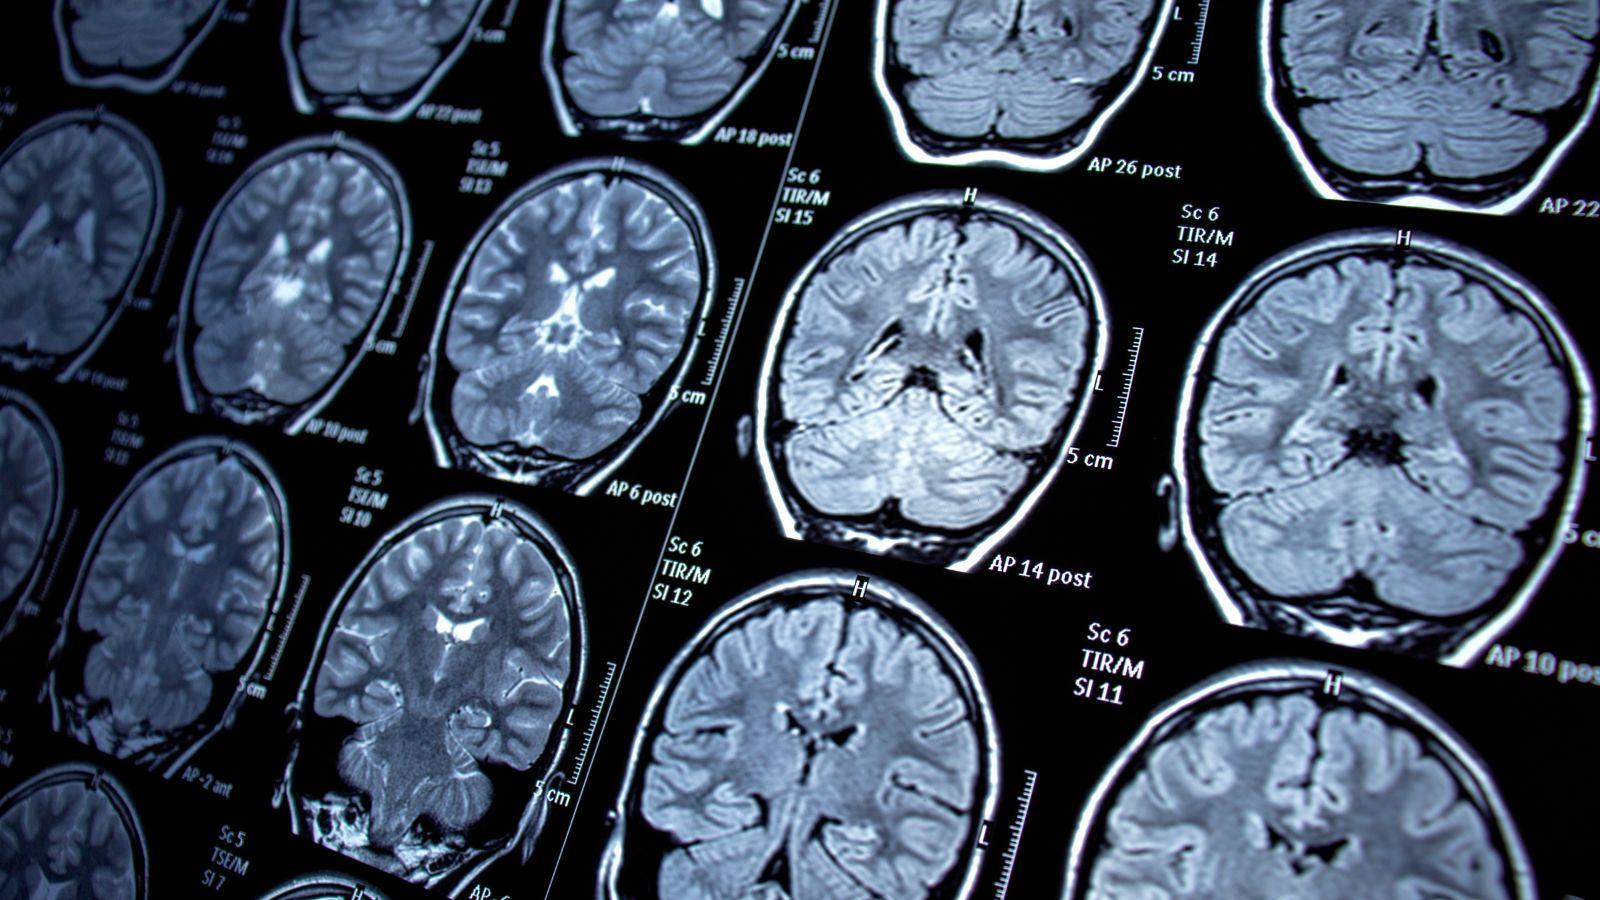

Cuando se presentan las primeras crisis epilépticas en los pacientes es necesario realizar estudios como el electroencefalograma o la resonancia magnética craneal para iniciar, de inmediato, el tratamiento farmacológico.